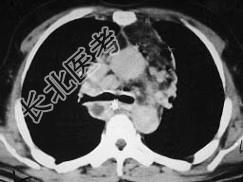

- 单项选择题男,64岁, 患糖尿病,最近三天出现发热, 伴颈静脉显露,结合CT图像, 选择最可能的诊断 ( )

A、坏死性纵隔炎

B、纵隔淋巴瘤

C、侵袭性胸腺瘤

D、恶性畸胎瘤

E、纵隔脓肿